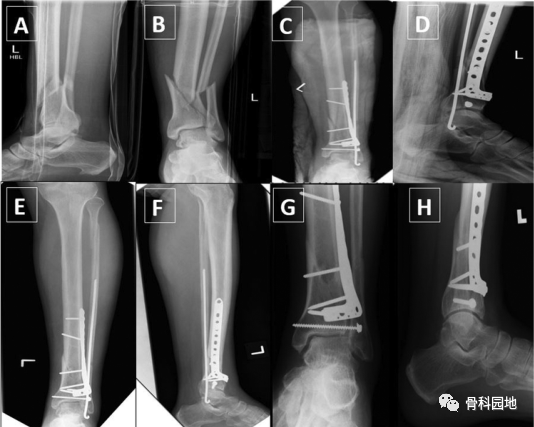

一、没有腓骨固定的情况下使用前外侧胫骨远端钢板固定骨折

二、使用内侧胫骨板和腓骨钢板固定。

三、使用前外侧钢板固定胫骨和腓骨克氏针固定。